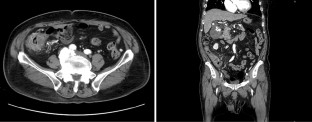

Lenvatinib is a standard molecular targeted agent for the first-line treatment of unresectable hepatocellular carcinoma. Here, we report a case of colitis induced by Lenvatinib treatment in a patient with hepatocellular carcinoma. A 78-year-old man previously treated with Lenvatinib for unresectable hepatocellular carcinoma was admitted to our hospital complaining of right lateral abdominal pain without diarrhea. Our endoscopic findings showed multiple ulcers and erosions on his ascending colon, and he was diagnosed with colitis induced by Lenvatinib treatment. After the discontinuation of Lenvatinib, his colitis improved, and he resumed Lenvatinib at a lower dose. Colitis is a rare adverse event of Lenvatinib, and this is the first detailed report of colitis induced by Lenvatinib with endoscopic findings.

Fig. 3